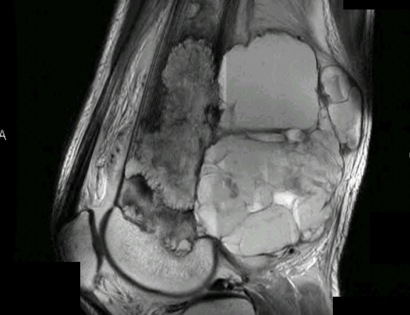

MRI of a Telangiectatic Osteosarcoma